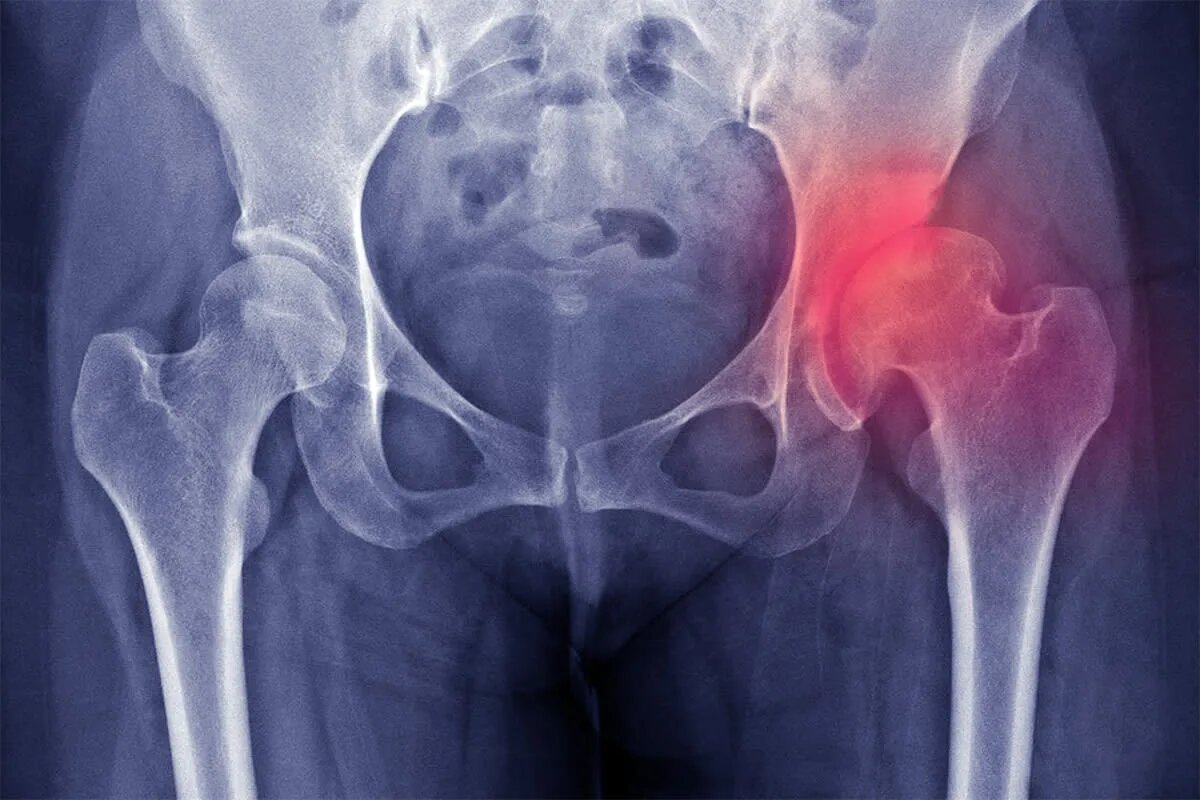

Тазобедренный сустав — один из самых нагруженных в теле. Он соединяет ногу с телом и позволяет нам ходить, поворачиваться, садиться, вставать. Его основа — головка бедренной кости, которая входит в углубление тазовой кости. Между ними находится прочный и гладкий хрящ — он служит как подушка и смазка, предотвращая трение костей.

При коксартрозе этот хрящ постепенно истончается, покрывается трещинами, теряет эластичность. Со временем он почти полностью исчезает, и кости начинают тереться друг о друга. Это вызывает воспаление, боль, ограничение движений и деформацию сустава. Процесс необратим, но его можно замедлить — особенно если начать вовремя.

• Рентген тазобедренного сустава — главный метод диагностики. Показывает, насколько сужена суставная щель, есть ли костные разрастания.